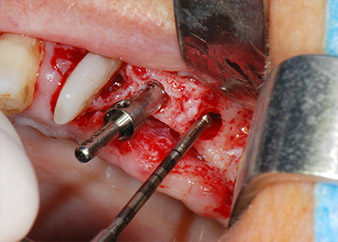

Prior to implant placement, infected tissue was removed from the alveolar bone in the implant site and around the abutment teeth with an insert originally designed for bone shaping and collecting bone chips (Piezomed, insert B5) (Figs. 6 and 7).

Implant beds were prepared at sites 25 and 26 with rotary instruments, used in a contra-angle handpiece with a 20 : 1 transmission ratio with an updated powerful implant motor (Implantmed, W&H) (Fig. 8).